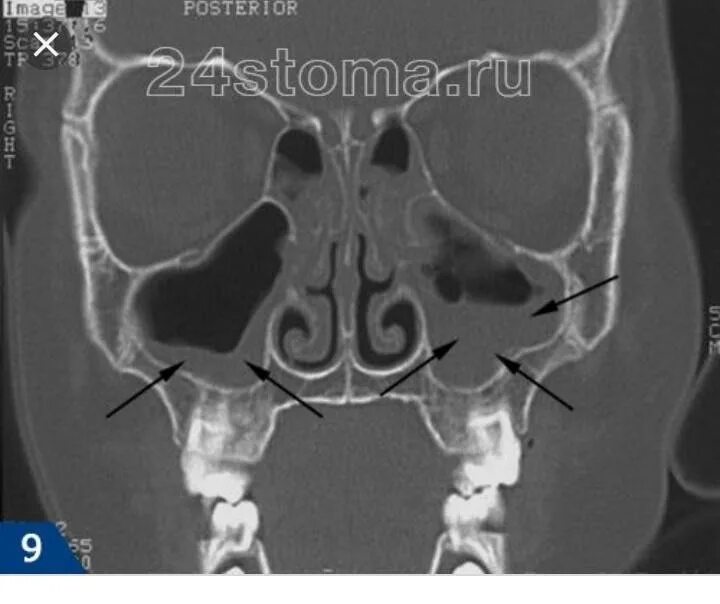

Утолщение верхнечелюстной пазухи что это значит